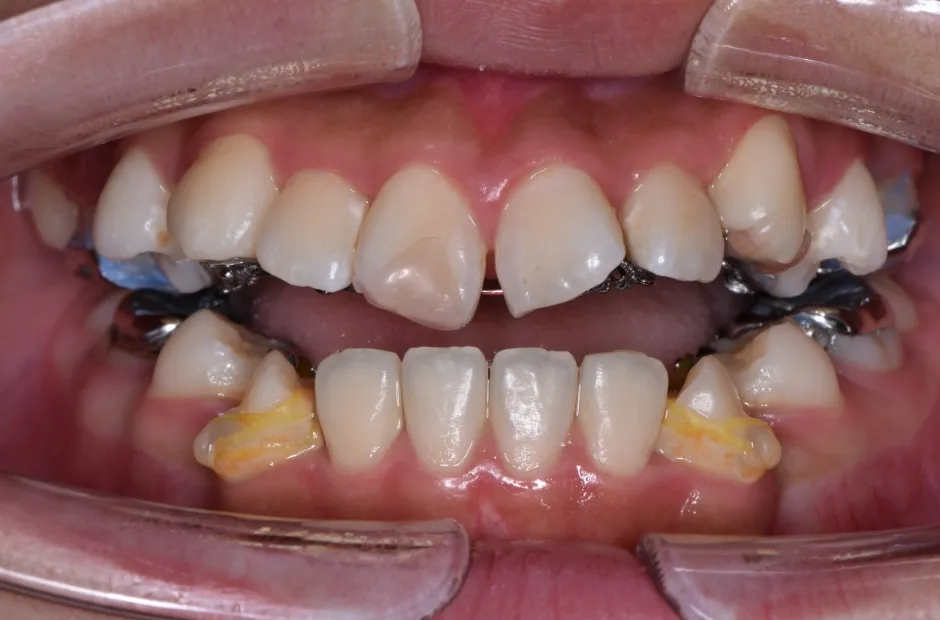

治療症例

ブラケット矯正

前歯部反対咬合

| 診断名・主訴 | 前歯部反対咬合 |

|---|---|

| 年齢・性別 | 14歳・男性 |

| 治療期間・回数 | 1年2か月 |

| 治療に用いた主な装置 | ブラケット矯正 |

| 抜歯部位 | なし |

| 治療費 | 60万円(税抜) |

| リスク・副作用 | 装置による違和感・疼痛・歯肉退縮・歯根吸収・虫歯のリスクなど |

治療中